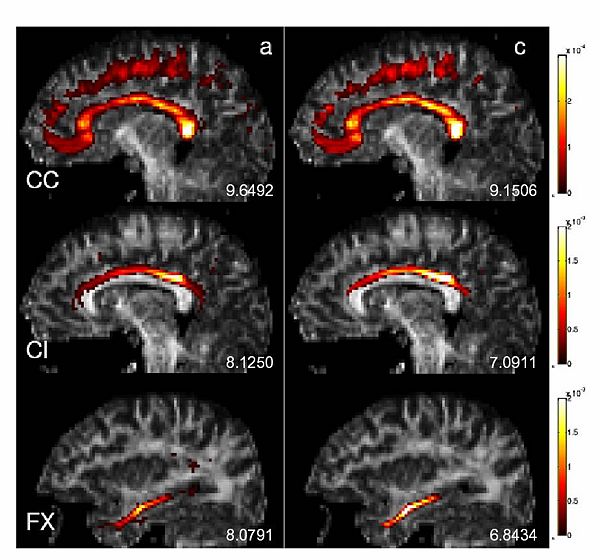

Corpus Callosum, Cingulum and the Fornix were selected for further investigation because of the specific challenges they present. These three structures are in close proximity with each other, and that results in many mislabeled fibers when labeled using a high dimensional atlas (see figure below (left)). Their close proximity also results in a number of trajectories deviating from one structure to another. These are precisely the sorts of artifacts we wish to reduce through learning common spatial distributions of fiber bundles from a group of subjects.

We also constructed two different atlases to compare the effects of labeling algorithms on the quality of resulting group maps. The first one is constructed using the initial labels from the high dimensional atlas. A second one is built using the proposed algorithm: